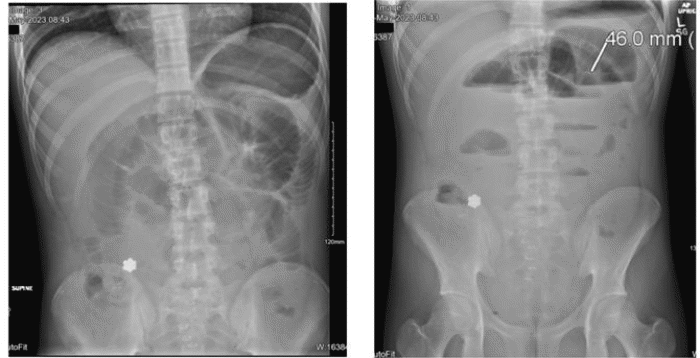

Contrast-enhanced CT scan of the abdomen and pelvis revealed findings consistent with mechanical obstruction. A transition point abutting the abdominal wall at the prior projectile injury site was noted proximal to the ileocolic anastomosis (Figure 3). A small bowel follow-through demonstrated small amounts of contrast in the distal small bowel loops at an 8-hour delay, indicating possible incomplete obstruction (Figure 4). Following discussion with the patient and guardian, a decision was made to perform a re-exploratory laparotomy.

Figure 3. CT Depicting Mechanical Small Bowel Obstruction at Prior Injury Site. Published with Permission

Axial view demonstrating the transition point abutting the fascial defect in the abdominal wall

(C) Axial view  of the ileocolic anastomosis (green arrow)

(D) Sagittal view of the ileocolic anastomosis (green arrow)